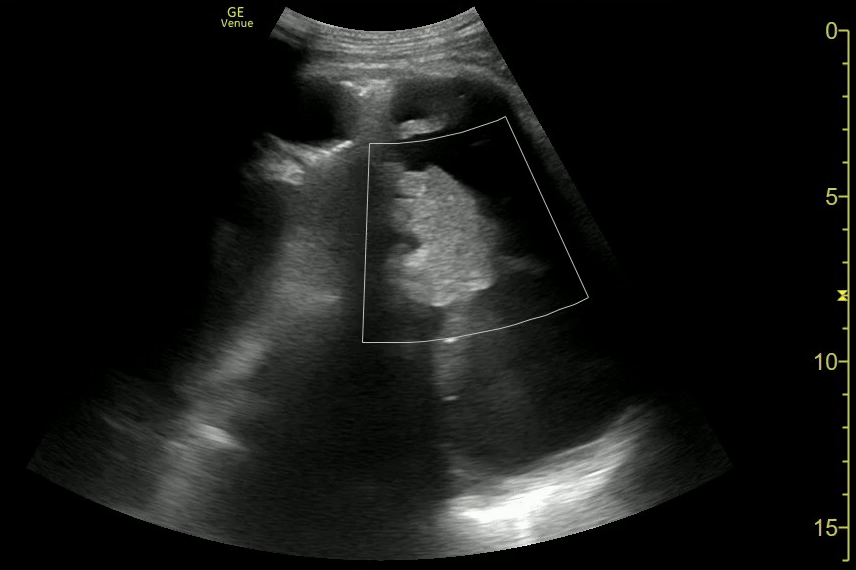

Prox Ureteral Stone, Sponge Kidney

Mid Ureter Obstructing Stone